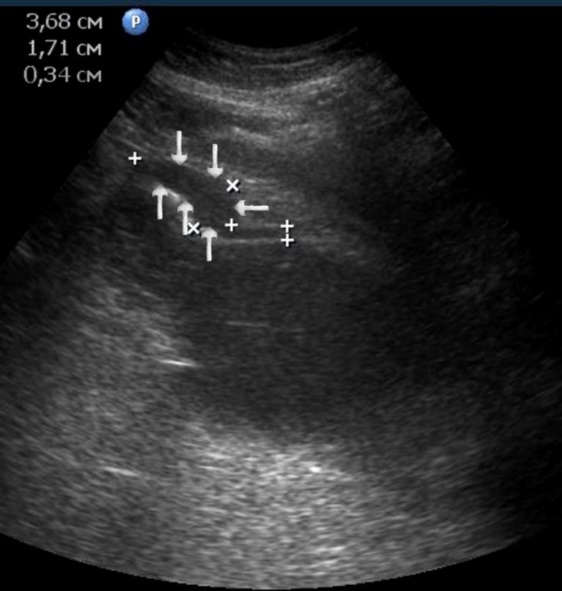

Figure 10.The gastric carcinoma of diffuse infiltrative form. An area with a local thickening up to 1,7 cm, a length of 3,68 cm, is visualized on the anterior wall of the antrum (arrows). The thickening of the normal stomach wall is 0,34 cm.

T2 stage of diffuse carcinoma was recorded in 14 cases – among them 5 cases of ulcerating forms, 5 cases of infiltrative ulcerative forms and 4 cases of diffuse infiltrative forms. Gastroscopy diagnosis was established in all 10 cases of ulcerative and infiltrative ulcerative forms of gastric carcinomas and in 3 cases of diffuse infiltrative forms. Ultrasound diagnosis was established in 13 cases of diffuse carcinoma, except for one case where the location of the ulcerative form was in the fundus of the stomach (Figure 8, Figure 9, Figure 10).

T3 stage of polypoid form was recorded in one case, ulcerative form – in 11 cases, infiltrative ulcerative forms – in 21 cases and diffused infiltrative forms – in 8 cases. The Sonographic features of infiltrative ulcerative form of gastric carcinoma was shown as local uneven thickening of the stomach wall with a length of up to several centimeters with intermittent images and ulceration of the mucosa (Figure 11). The Ulcerative form of gastric carcinoma was shown as a raised margins surrounded by a thickened gastric wall with irregular margins (Figure 12). Gastric carcinomas of diffuse infiltrative form is illustrated as a diffuse thickening of the muscle layer, a smooth contour, discontinuous mucosal image without ulceration and involvement of the serous membrane in the process (Figure 13).